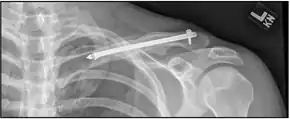

X-ray of a left clavicle fracture

X-ray of the above comminuted fracture treated with an intramedullary fixation device

For breaks in the middle of the clavicle in children surgery resulted in faster recover but more complications.[11] The evidence for different types of surgery for breaks of the middle part of the clavicle is poor as of 2015.[12]

A discontinuity in the bone shape often results from a clavicular fracture, visible through the skin, if not treated with surgery. Surgical procedures often call for open reduction internal [plate] fixation where an anatomically shaped titanium or steel plate is affixed along the superior aspect of the bone by several screws. In some cases, the plate is removed after healing due to discomfort, to avoid tissue aggravation, osteolysis or subacromial impingement. This is especially important with a special type of fixation plate called hook plate.[14] With anatomical plates plate removal is considered an elective procedure that is rarely necessary. An alternative to plate fixation is elastic TEN intramedullary nailing. These devices are implanted within the clavicle's canal to support the bone from the inside. Typical surgical complications are infection, neurological symptoms distal the incision (sometimes to the extremity), and nonunion of the bone (failure of the bone to properly fuse together).